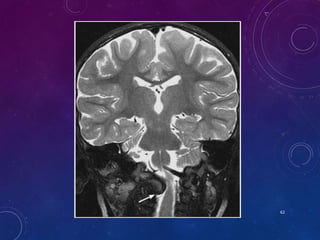

OS ODONTOIDEUM

• Failure of basal dental and axis body ossification centers to fuse at LS.

• Non-fusion is below the level of transatlantal lig - a/w instability.

• Orthotopic and dystopic (Os avis).

• Radiographic features:

• Smooth, well-corticated ossicle at the superior ossicle of a hypoplastic dens

• around half the size of a normal dens

• a/w hypertrophied and rounded anterior arch of the atlas

• Posterior arch is hypoplastic

43

• #45 Os odontoideum in an 8-year-old child presented with multiple cerebellar and thalamic strokes. b CT scans show multiple small infarcts of left cerebellar hemisphere and thalamus secondary to multiple vertebrobasilar emboli. Cerebral angiogram shows os odontoideum with a corrugated horn-like inferior edge (arrow) with anterior C1– C2 subluxation and stretch injury to the vertebral artery.

• #46 Coronal 2D CT through plane of os odontoideum. The ossicle has defined cortical borders. There is a gap below it and a hypoplastic dens present. i Midsagittal T2-weighted MRI of CVJ. The cervicomedullary junction is draped over the superior axis body. Note the cruciate ligament in front of the axis; below the ossicle.